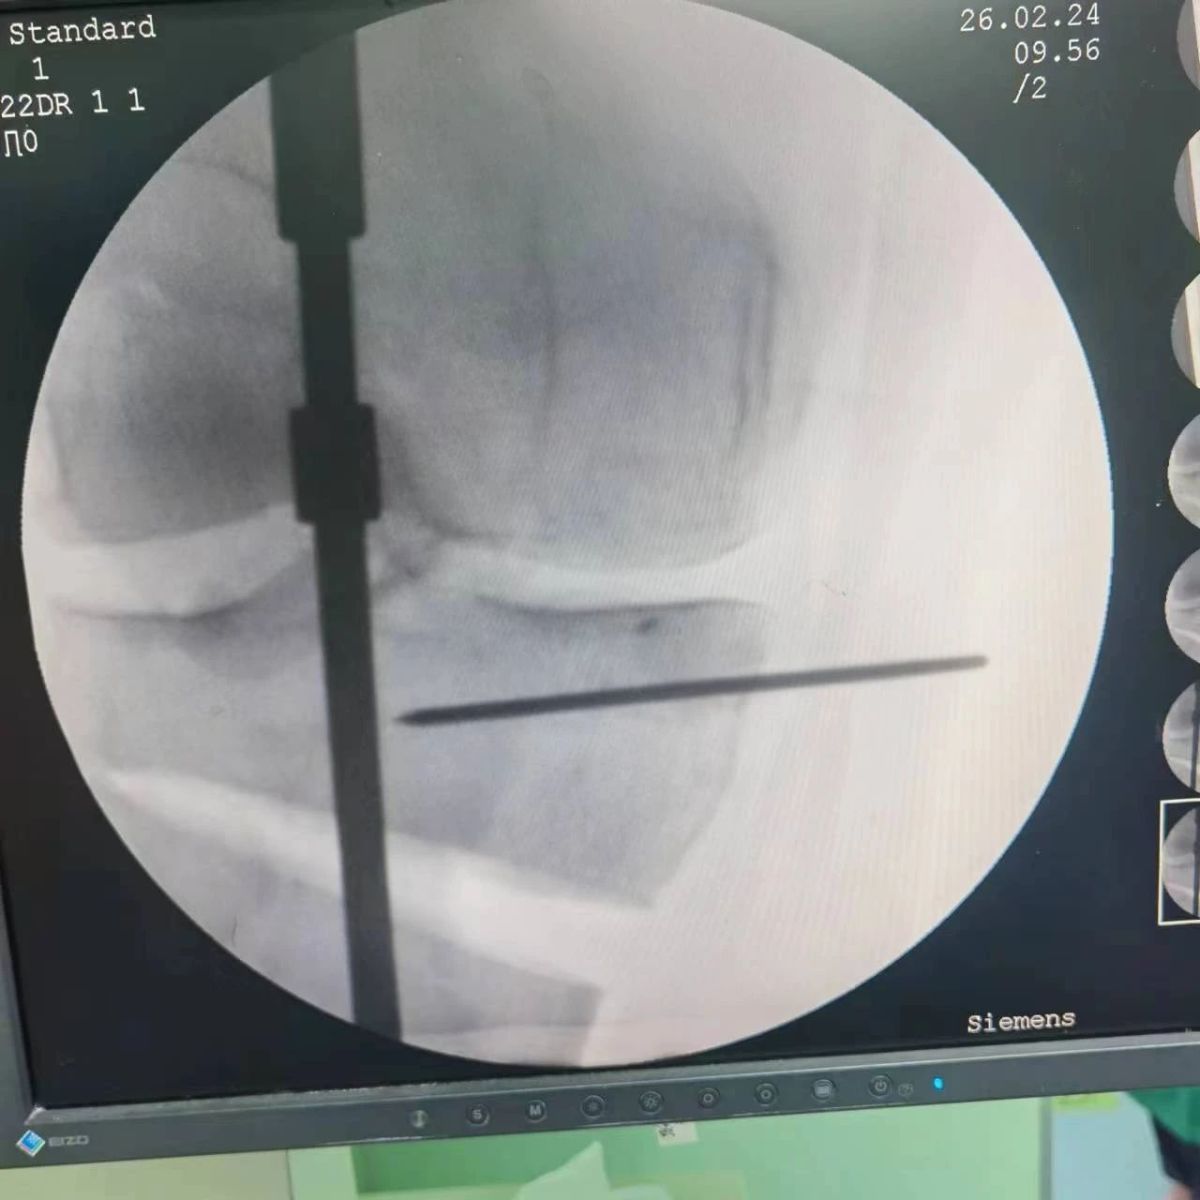

2月26日,漯河市骨科醫(yī)院(漯河醫(yī)專(zhuān)二附院、漯河市立醫(yī)院)膝關(guān)節(jié)外科、運(yùn)動(dòng)損傷科(骨六科)在保膝治療方面取得了新的突破,李付彬主任帶領(lǐng)岳龍等團(tuán)隊(duì)醫(yī)師,順利完成“計(jì)算機(jī)精準(zhǔn)術(shù)前規(guī)劃聯(lián)合3D打印截骨導(dǎo)板輔助脛骨高位截骨治療膝關(guān)節(jié)骨性關(guān)節(jié)炎”的手術(shù),這在漯河市尚屬首例!

患者為一名45歲男性,查體及X片可見(jiàn)明顯的膝內(nèi)翻,內(nèi)翻畸形主要來(lái)源于脛骨近端,關(guān)節(jié)鏡下可見(jiàn)內(nèi)側(cè)間室軟骨全層磨損,疼痛較重,年紀(jì)輕輕幾乎喪失工作能力。對(duì)于這種日?;顒?dòng)需求比較大的患者朋友,我們盡最大可能給予保膝治療,李付彬主任給患者詳細(xì)講解了保膝治療的方案(脛骨近端高位截骨)及預(yù)期效果,給患者帶來(lái)了極大希望。為了更精確、更微創(chuàng)的治療,李付彬主任團(tuán)隊(duì)緊跟國(guó)內(nèi)外科技前沿,采用計(jì)算機(jī)精準(zhǔn)術(shù)前規(guī)劃,并設(shè)計(jì)3D打印截骨導(dǎo)板,力求給患者帶來(lái)更精準(zhǔn)、更安全的手術(shù)效果。

李付彬主任團(tuán)隊(duì)通過(guò)精準(zhǔn)術(shù)前規(guī)劃,設(shè)計(jì)目標(biāo)力線及調(diào)整撐開(kāi)角度,轉(zhuǎn)化成需要撐開(kāi)的高度,最終設(shè)計(jì)出同等高度的填充塊,術(shù)中驗(yàn)證力線調(diào)整與術(shù)前規(guī)劃完全一致!

鋼板位置、螺釘位置及長(zhǎng)度均可通過(guò)術(shù)前規(guī)劃計(jì)算,術(shù)中通過(guò)定位操作,基本與術(shù)前規(guī)劃一致,手術(shù)快速高效完成,外側(cè)合頁(yè)保留完整。無(wú)任何并發(fā)癥出現(xiàn)。術(shù)后見(jiàn)鋼板位置及力線糾正近乎完美!

OWHTO手術(shù)效果依賴(lài)于多個(gè)數(shù)據(jù)參數(shù),比如:截骨的入點(diǎn)、合頁(yè)位置的選擇、截骨線的深度、截骨線的方向、撐開(kāi)的距離等,依托計(jì)算機(jī)術(shù)前精準(zhǔn)規(guī)劃和3D打印導(dǎo)板可輔助醫(yī)生精準(zhǔn)控制上述參數(shù),使截骨更準(zhǔn)確,真正達(dá)到精確的力線調(diào)整,減少術(shù)中透視次數(shù),縮短手術(shù)時(shí)間并降低手術(shù)風(fēng)險(xiǎn),從而使得OWHTO得到更好的應(yīng)用,造?;颊?。